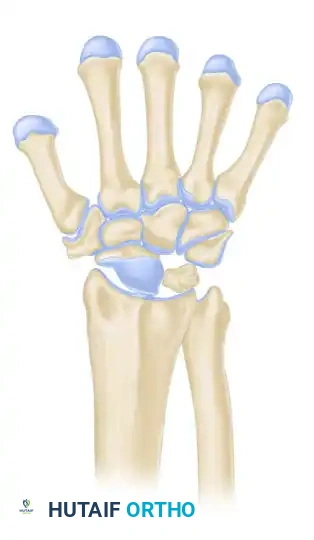

LICHTMAN CLASSIFICATION OF KIENBÖCK DISEASE

The staging classification proposed by Lichtman et al. is the universally accepted framework for guiding surgical decision-making. The natural history, if left untreated, progresses from sclerosis to fragmentation, carpal collapse, and ultimately pancarpal arthritis.

Stage IIIB

- Description: Lunate fragmentation is accompanied by fixed rotation of the scaphoid (dorsal intercalated segmental instability - DISI pattern) and proximal migration of the capitate.

- Treatment: Proximal row carpectomy (PRC) or STT fusion. The internal collapse pattern must be addressed.